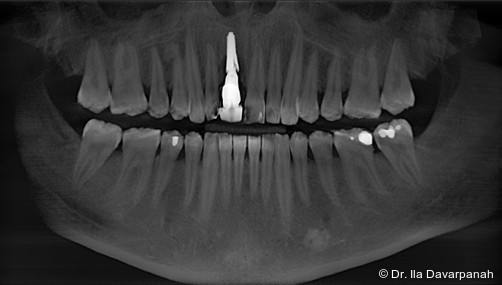

Postoperativ kam es trotz korrekter Implantatpositionierung und regelrechter Sofortversorgung zu einer Fraktur des Implantatkörpers im Bereich der Implantatschulter. Die radiologische Diagnostik mittels Röntgen und DVT zeigte ein Aufplatzen des Implantats im Übergangsbereich zwischen Konusverbindung und Implantatplattform. Das Frakturmuster deutete auf eine strukturelle Überlastung im hoch beanspruchten Schulterbereich hin. Implantatfrakturen stellen insgesamt eine seltene, jedoch für Patient und Behandler belastende Komplikation dar. Sie treten bevorzugt in Regionen mit erhöhten Biege- und Querkräften auf, insbesondere in der Frontzahnregion und bei frühzeitiger funktioneller Belastung.

Im vorliegenden Fall lag der Fokus der Analyse weniger auf der chirurgischen Umsetzung oder der Indikationsstellung, sondern auf der mechanischen Belastbarkeit. Der Schulterbereich eines Implantats ist biomechanisch besonders exponiert, da hier funktionelle Kräfte konzentriert eingeleitet werden. Unterschiedliche konstruktive Ansätze versuchen, diese Belastung durch Modifikationen der Verbindung oder der Kraftübertragung zu reduzieren. Insbesondere bei Sofortimplantationen mit Sofortversorgung ergeben sich erhöhte Anforderungen an die mechanische Reserve des Systems.